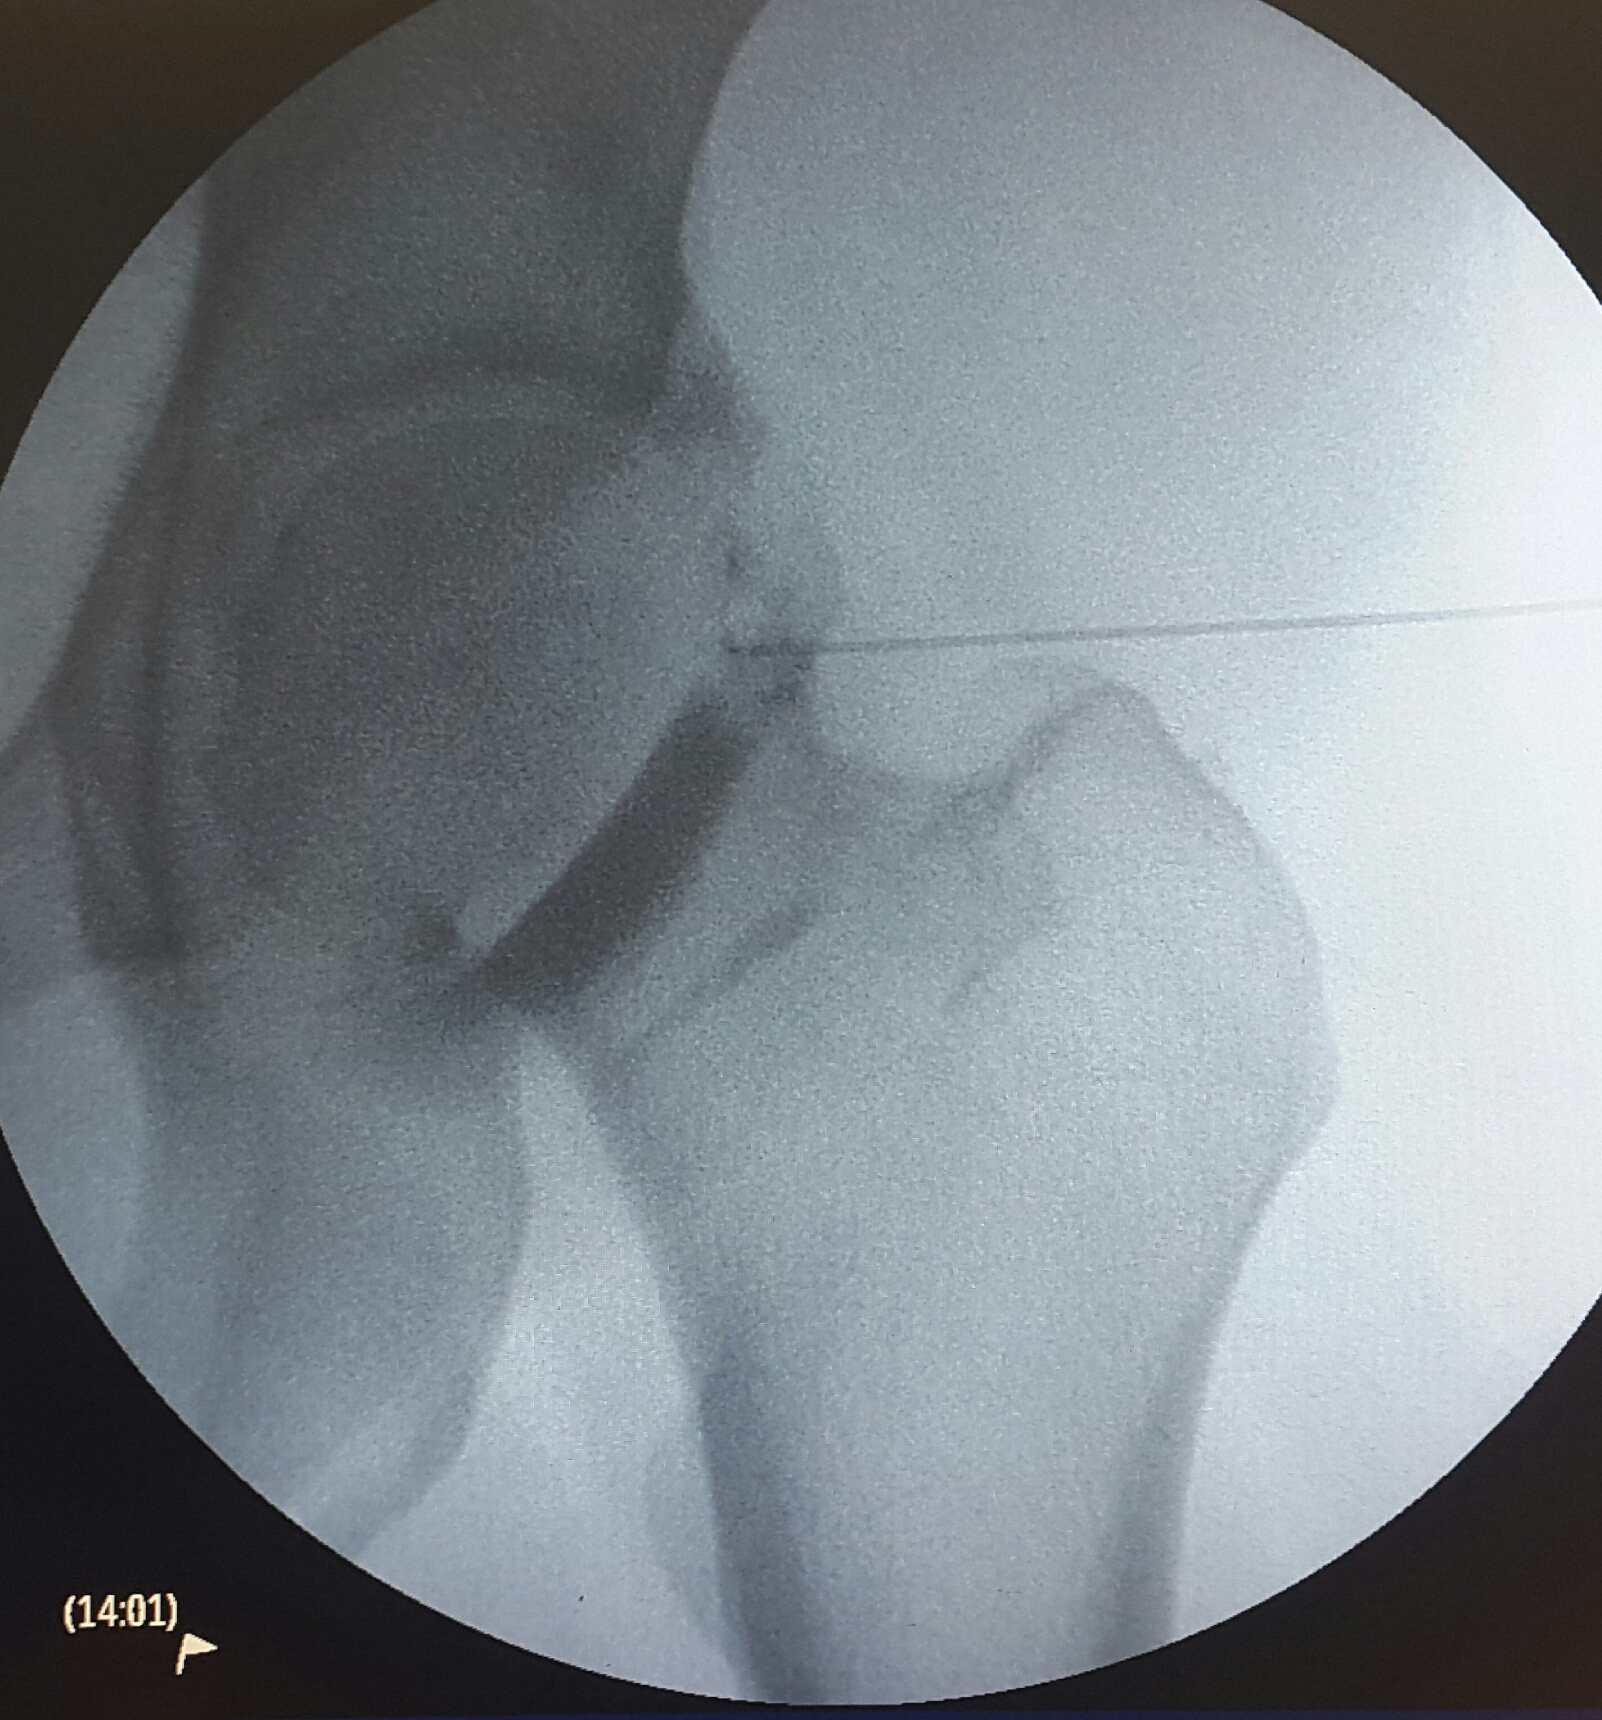

Η αποτελεσματικότητα των ενδαρθρικών εγχύσεων στην οστεοαρθρίτιδα του ισχίου

Οι ενδαρθρικές εγχύσεις αποτελούν έναν τρόπο μεσοπρόθεσμης αντιμετώπισης των συμπτωμάτων για την οστεοαρθρίτιδα του ισχίου.  Οι συνηθέστεροι φαρμακευτικοί παράγοντες που χρησιμοποιούνται είναι τα κορτικοστεροειδή, το υαλουρονικό οξύ, οι βιολογικοί παράγοντες και οι συνδυασμοί των ανωτέρω.